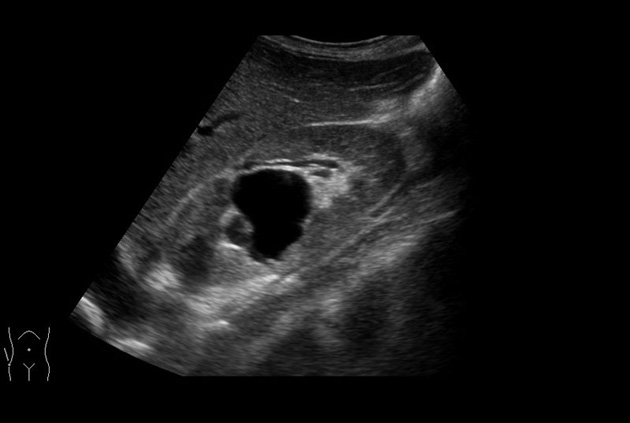

Superior guidance for all applications

Fujifilm Healthcare Americas is committed to designing tools that help surgeons navigate inside the human body and provide the necessary information to immediately make critical surgical decisions.

Fujifilm Healthcare's dedication to Surgeons provides outstanding ultrasound technology, professional support and the specialized tools necessary to best perform comprehensive real-time ultrasound imaging in Breast Surgery, General Surgery, Laparoscopic Surgery, Neurosurgery, Robotic Surgery and Surgical Oncology.

Arietta 70

Recognized for our outstanding image quality, outstanding system reliability and intuitive use of cutting edge technology, Fujifilm Healthcare remains the standard in the field of Surgery.